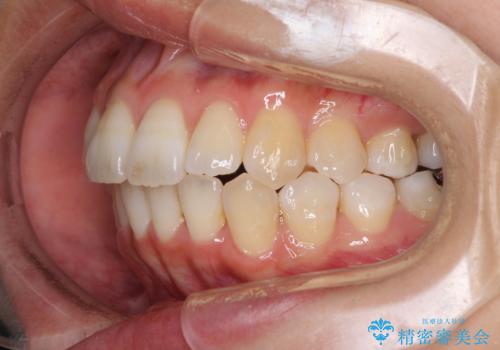

骨格的な問題を抱えた左奥以外は比較的早く咬み合わせが改善しましたが、左奥はどこで咬み合えば良いのか分からず、大変不便な思いをされていました。

ゴムかけにご協力いただき、最終的には反対咬合を改善することができ、患者様には大変満足していただきました。